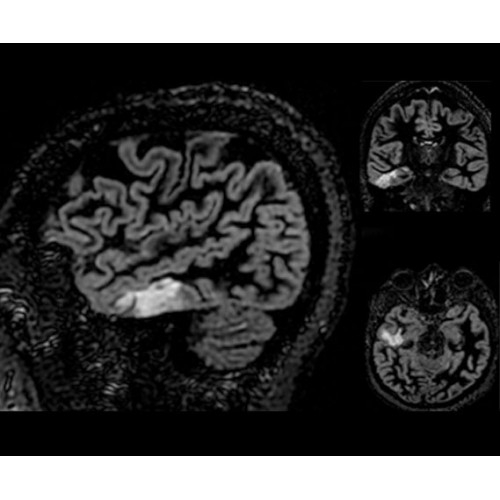

Кроме того, в результате использования технологии TOF и инновационной технологии реконструкции Q.Clear вы сможете добиться прекрасного соотношения сигнал/шум. А благодаря технологии нулевого времени эхо (ZTE) визуализировать костную структуру без ионизирующего излучения. Все эти разработки для улучшения качества сканирования и точности анализа помогут вам использовать весь потенциал ПЭТ/МРТ.

• МРТ с функцией нулевого времени эхо (ZTE) отличается точностью, возможностью персональных настроек и отсутствием ионизирующего излучения. Она приходит на смену традиционному исследованию на основе рентгеновского излучения. МРТ с функцией нулевого времени эхо (ZTE) на базе SIGNA ПЭТ/МРТ является более надежной и быстрой по сравнению с системами, использующими сверхмалое время эхо (UTE).

• Специальный пакет приложений для измерения и сравнения объемных изображений ЦНС с нормами поможет вам в диагностике нейродегенеративных заболеваний, а дополнительные инструменты визуализации — в постановке точного диагноза с помощью бета-амилоидов и радиоизотопных маркеров ФДГ.